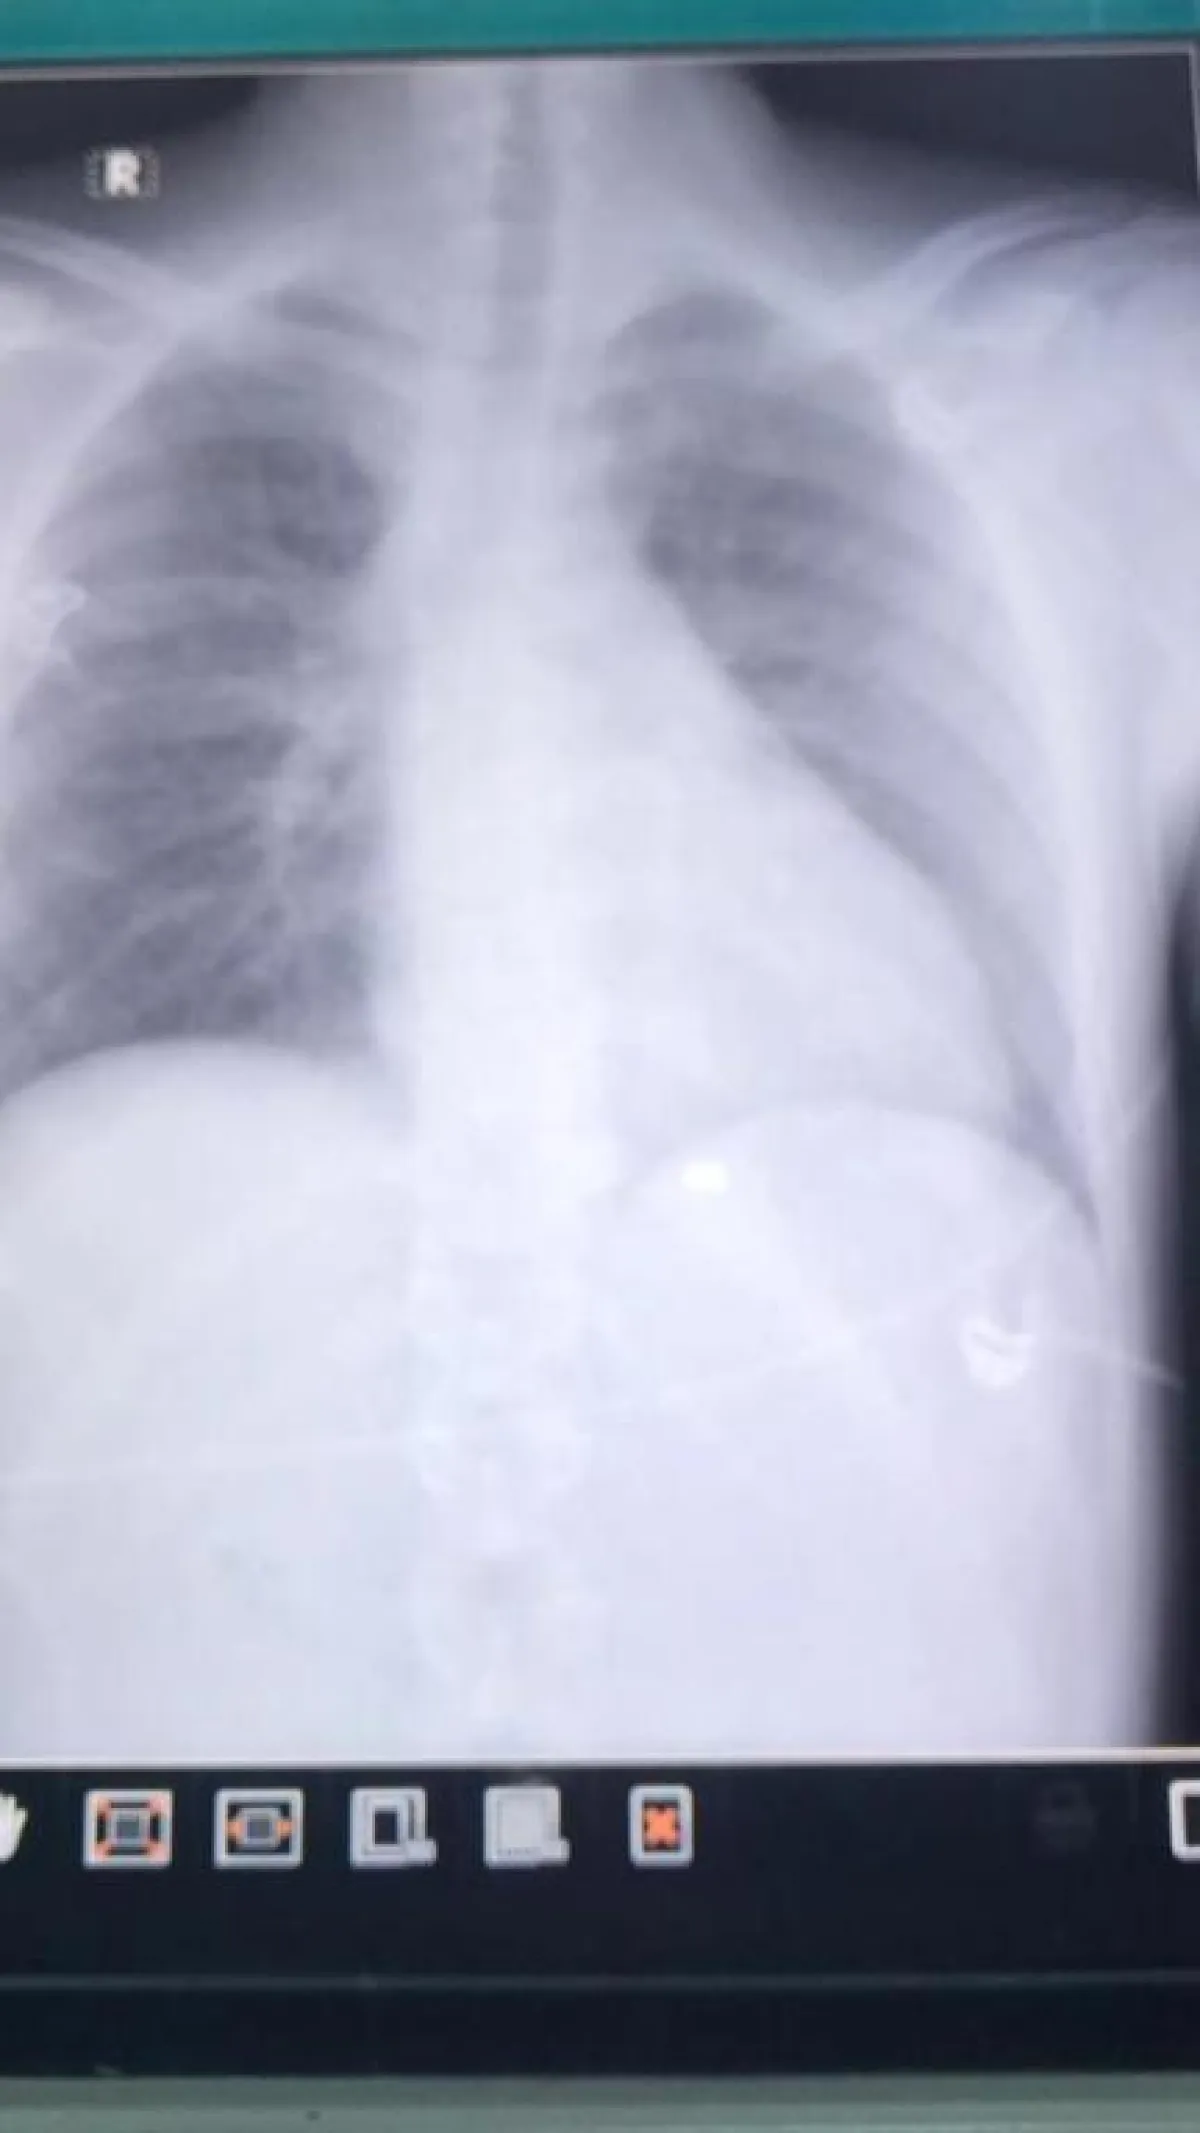

و في التفاصيل أستقبل قسم الطوارئ بالمستشفى مواطن يبلغ من العمر 17 عاماً حضر بواسطة سيارة اسعاف تابعة لإحدى المستشفيات الخاصة تعرض لطلق ناري في البطين الأيمن للقلب مع وجود نزيف شديد ، وتم التعامل مع الحالة على الفور لدى وصول المصاب لقسم الطوارئ، ونقله مباشرة إلى غرفة العمليات ، وإجراء عملية قلب مفتوح بشكل عاجل واستخراج الرصاصة وسحب التجمع الدموي في غشاء التامور المحيط بالقلب وترقيع جدار البطين الأيمن، وتم وقف النزيف من الصدر بمشاركة الدكتور فواز ألطف والدكتور محمد شفيق جراحين القلب والصدر وتم إنقاذ المريض بفضل من الله، ولا زال المصاب بالعناية المركزة في حالة مستقرة خاضعاً للعناية والمتابعة الطبية اللازمة .